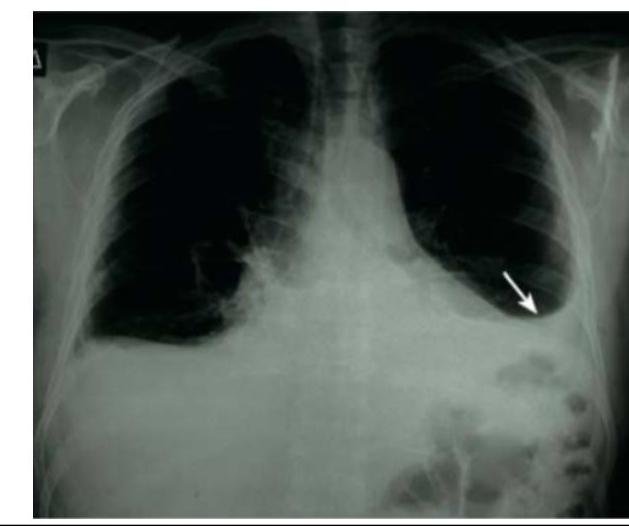

# DERRAME PLEURAL ## DEFINICIÓN El **Derrame Pleural** se define como la **acumulación anormal de líquido en la cavidad pleural** debido a una **producción excesiva** de este o a una **incapacidad para su depuración**. La **etiología** del **DP** depende de la región geográfica, de la edad del paciente y del centro donde se realice el diagnóstico. ## ETIOLOGÍA 1. Enfermedades Infecciosas 55.2 % 2. **Neumonías** y **derrame paraneumónico** 24.7 % 3. **Tuberculosis** / **VIH** 8.2 % 4. **Empiema** 11.3 % | **TRASUDADO** | **EXUDADO** | | :--: | :--: | | FRECUENTES: | FRECUENTES | | - **Falla del Ventrículo Derecho**<br>- **Cirrosis Hepática**<br>- **Hipoalbuminemia**<br>- **Diálisis Peritoneal** | - **Tuberculosis**<br>- **Malignidades**<br>- **Derrame Paraneumónico** | | MENOS FRECUENTES | MENOS FRECUENTES | | - **Hipotiroidismo**<br>- **Síndrome Nefrótico**<br>- **Estenosis Mitral**<br>- **TEP** | - **Infarto pulmonar**<br>- **Artritis reumatoide**<br>- **Enfermedades autoinmunes**<br>- **Pancreatitis** | | | - **Derrame benigno post-asbesto**<br>- **Quilotórax** | | RARAS | RARAS | | - **Pericarditis constrictiva**<br>- **Urinotórax**<br>- **Obstrucción de Vena Cava Superior** | - **Drogas**<br>- **Síndrome de uñas amarillas**<br>- **Infecciones fúngicas** | | - **Hiperestimulación Ovárica**<br>- **Síndrome de Meigs** | | # EPIDEMIOLOGÍA Edad media de presentación es 52 años. ## CLÍNICA Dependerá de la enfermedad subyacente y de la **cantidad de líquido** contenido en el **espacio pleural**. Datos sugestivos de **DP**: - **Disminución** / **ausencia** de los **movimientos respiratorios del lado afectado** - **Disminución de vibraciones vocales** - **Matidez a la percusión** - **Disminución o ausencia de los ruidos respiratorios** - La **tráquea** se puede desviar al lado contralateral (dependiendo de la cantidad de derrame) ## LARGE EFFUSIONS **PAIN** (**PLEURISY**) **SHORTNESS of BREATH** **WORSE WHEN LYING DOWN**   © Copyright 2021-2022 Joyas ENARM - Todos los derechos reservados - # DIAGNÓSTICO ## LABORATORIO ## PCR - Marcador sensible para evaluar la progresión de una **Neumonía**. - Recomendado para **evaluación inicial y seguimiento** de tipo **infeccioso**. ## LEUCOCITOS - En **pacientes** con **Neumonía** pueden aparecer 3 días después de iniciar la **infección**. ## IMAGEN ## RADIOGRAFÍA TÓRAX (AP Y LATERAL) 1ra elección: en pacientes con sospecha clínica de **DP**. - Cantidad normal de LP es 10-15 ml. - 50 - 75 ml de **líquido pleural** - **Borramiento del ángulo costodiafragmático** (**signo del menisco**) - >200 ml de **líquido pleural** - **Borramiento de ángulos cardiofrénico y costodiafragmático**. **Derrrames pequeños** pueden detectarse en una **radiografía en decúbito lateral** sobre el lado afectado. **Derrames Masivos** ocupan todo el hemitórax, desplazan mediastino al lado opuesto.  **Derrame Pleural izquierdo** (**Signo del Menisco** en la flecha)  **Radiografía lateral** izquierda, se observa la medición del **derrame pleural** en **decúbito lateral**. # ULTRASONIDO TÓRAX Es más específico y sensible que la **radiografía**. ## Indicaciones: - Identificar **DP** pequeños. - Establecer localización para efectuar **Toracocentesis**, **Biopsia Pleural** o colocar **sonda**. - Identificar **loculaciones pleurales**. - Diferenciar entre **derrame** y **engrosamiento pleural**. ## TOMOGRAFÍA Reservada para casos más complicados, como los que se debe caracterizar la **extensión parenquimatosa** o la presencia de un **absceso pulmonar**, cuyo resultado puede repercutir en la **Qx**. Si se realiza con contraste, es útil para diferenciar una **consolidación pulmonar**, que capta el contraste, de un **DP** que se muestra hipodenso. Se identifican **colecciones interlobulares**, en **pleura mediastínica** y de pequeño tamaño paravertebrales. Útil en **diagnóstico de empiema**, cuando la pleura realza intensamente alrededor del **líquido**. **Hallazgos que sugieren malignidad**: - **Engrosamiento pleural nodular** - **Engrosamiento pleural mediastinal** - **Engrosamiento parietal** > 10 mm - **Engrosamiento pleural circunferencial**. # TORACOCENTESIS DIAGNÓSTICA - **Derrame** >10 mm de profundidad en la **radiografía lateral**, en asociación a **trauma torácico reciente**, **cirugía reciente** y en **sepsis** - **TOMAR MUESTRA LÍQUIDO PLEURAL**. - **Derrame** menos de 10 mm - **NO SE TOMA MUESTRA DE LP** (a menos que en su curso aumente el tamaño o se agreguen datos de **sepsis**). - **Derrame** + **Sospecha de Infección** - **Hemocultivo** + **Cultivo de LP**. ## Técnica: 1. Tomar 50 ml de **Líquido pleural** con aguja de 21 G. 2. 5 ml a bacteriología. 3. 2-5 ml a citoquímico con **tinción de Gram**. 4. 20-40 ml a citológico. 5. Una parte en **jeringa heparinizada** para **gasometría**. Se puede guiar por **Ultrasonido**.  ## CRITERIOS DE LIGHT Clasifican correctamente el 98 % de los **DP** en **Exudado** y **Trasudado**. | CRITERIO | TRASUDADO | EXUDADO | | :--: | :--: | :--: | | **Relación DHL Pleural / Suero** | Menor 0.6 | Mayor 0.6 | | **Relación Proteína Pleural / Suero** | Menor 0.5 | Mayor 0.5 | | **DHL en líquido pleural** | Menor a 2/3 partes del límite superior normal de DHL plasmática | Mayor a 2/3 partes del límite superior normal de DHL plasmática | | **Colesterol** | Menor a 43 | Mayor a 43 | | **Gradiente Sérico Pleural de Albúmina** | Mayor a 1.2 | Menor a 1.2 | ## CITOLOGÍA Y BIOPSIA - Se recomienda en caso de **sospechar malignidad**. Debe repetirse si el estudio inicial es negativo y añadir toma de muestras mediante **Biopsia**. - La combinación de estas pruebas mejora el **diagnóstico** para **DP maligno** (o **Tb Pleural**). - Se debe realizar **Biopsia guiada por TAC** en sospecha de **DP maligno** y **pH** y **Glucosa bajos en el LP**. ## ADENOSIN DESAMINASA (ADA) Cifras > 35 UI en el **LP** son sospechosos de **Tuberculosis Pleural** o en su defecto **BIOPSIA PLEURAL**. # TRATAMIENTO ## ANTIBIÓTICO La selección se realiza teniendo en cuenta el origen comunitario del **derrame pleural**, paciente, peculiaridad geográfica y local. Se debe iniciar de forma **empírica y precoz**, incluyendo cobertura para **anaerobios** y ajustarlo con el **cultivo**. ## 1ra elección: PENICILINA **Alergia** - **CLINDAMICINA** (sola o + **Quinolona** o **Cefalosporina 3a Generación** = **CEFTRIAXONA**). Si el origen es un **S. aureus meticilino-resistente** o **S. pneumoniae resistente a Cefalosporinas**: - **Vancomicina** o **Linezolid**. Los **aminoglucósidos** tienen escasa penetración en la pleura, no están indicados. - La **mala evolución clínica durante el tratamiento con antibióticos** debe conducir a **repetir toma de muestras de laboratorio, líquido pleural** ecluso **colocar sonda pleural**. - Al identificar la **presencia de organismos** por **tinción de Gram** y/o **cultivo de una muestra de LP no purulento** indica que se ha establecido la **infección pleural** y debe conducir a **drenaje torácico**. ## TORACOCENTESIS EVACUADORA (SONDA TORÁCICA) La **evacuación** debe efectuarse lentamente para evitar **edema pulmonar de reexpansión**, monitorizando la **presión pleural** durante la evacuación del **líquido** y en **adultos con DP maligno** hasta 1.5 L en una ocasión. Indicada en: - **Derrame Paraneumónico complicado** (pH<7.2, Glucosa <60 mg / dL). O Si no cumple con esos criterios, puede ser tratado únicamente con **antibióticos**. - **Empiema**. - **Derrame loculado**. - **Microorganismos en el LP**. - **Neumotórax asociado**. - **Paciente séptico**. ## FIBRINOLÍTICOS ## 1ra elección en pacientes con Empiema o Derrame Loculado.  - El **exudado** es más viscoso por alto contenido de **fibrina**, formando **septos y loculaciones**. - Si se coloca **sonda pleural** y **antibiótico** no resolvería el problema. **Fármacos** - **Estreptoquinasa, Uroquinasa o Alteplasa (aTP)**. # TRATAMIENTO QUIRÚRGICO ## Cirugía Torácica Video-Asistida (VATS) Indicado si el **DP** está en fase **fibrinopurulenta** u **Organizada** y en **DP persistente** por 2 o más semanas. Es el **Gold Standard** del manejo del **DP complicado** en fase II o III.  ## TORACCTOMÍA - Si no se ha logrado una **expansión pulmonar completa** y existe **fuga aérea** o **salida de pus por el drenaje**. - **Falla** en las **maniobras terapéuticas** presentadas con anterioridad. - Envío a tercer nivel de acuerdo a los resultados.  ## EMPIEMA NECESSITATIS - **Pus dentro de la cavidad pleural** que irrumpe hacia los **tejidos blandos, tejido subcutáneo** y hasta la **piel**. - Se trata su **etiología** (**Tb, Micosis, Mycobacterias atípicas, empiema bacteriano crónico**). - **Drenaje Percutáneo** + **Drenaje Pleural**.